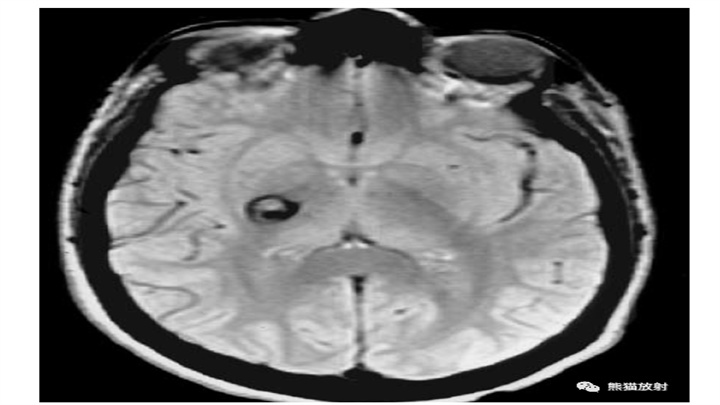

由海绵状血管瘤破裂引起的IPH。22岁女性,内囊后肢局部出血性病变。MR可见含铁血黄素低信号环,证明其与海绵状血管瘤破裂有关。